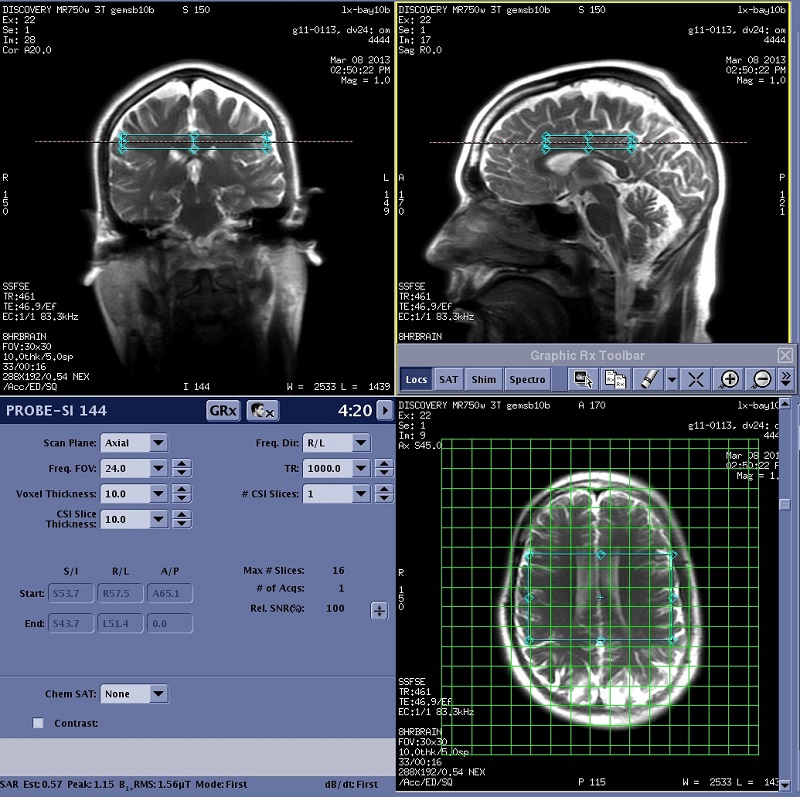

PROBE 2D CSI: acquire a scan

In order to display the localizer image in READY View, the center of each reference slice must be within 0.8 mm of each CSI slice. If a slice that meets this criterion does not exist in the selected reference series, READY View displays an error message, "Localizer loading failed, no matching image". Click OK to the error message. READY View launches, but an image does not display in the lower-left viewport. To avoid this problem, follow these guidelines when prescribing a 2D CSI scan.

Important: Do not save the 2D CSI protocol as an oblique plane. Save the protocol as an axial plane and then change the plane to oblique when you are viewing/editing the series.